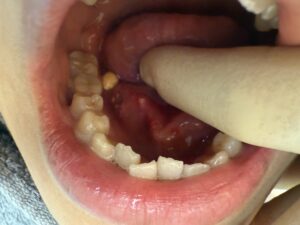

実際の写真

写真2枚目の向かって左側の白っぽいものが唾石です。問題なく摘出して縫合しました。このように当院では歯科口腔外科領域の外科手術に精通しており様々な症例に対応しております。ただし、当院でも無理な手術を行うことはせず、本当に難しい症例の場合には稀に大学病院をご紹介させていただくことがあります。あくまで安全性を最優先で手術を行っております。